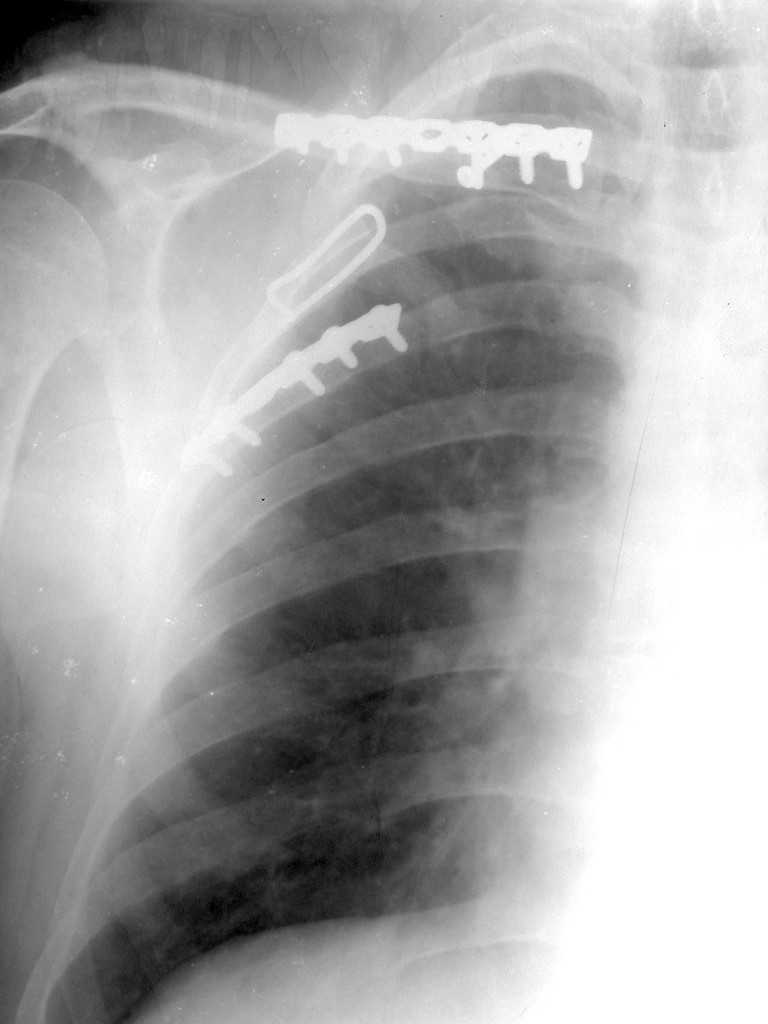

Здравствуйте Виталий Геннадьевич!

К сожелению доктор который занимается грудной клеткой в отпуске, у себя нашёл только вот этот снимок

С Уважением А.Миронов

Всё зависит от типа нестабильности грудной клетки. Стабилизация проводится от 4 по 8 активно участвующих в дыхании рёбер. Т.е если имеется "створка" фиксируютс рёбра по одноё линии. Разрез продольный по линии переломов из которого фиксируются 2-3 ребра, если имеется "клапан", то фиксируютяс 2-3ребра по одной линии и 2-3ребра по другой линии. Репозиция несложная, фиксация реконструктивной пластиной, в хрящевой части лучше LCP.